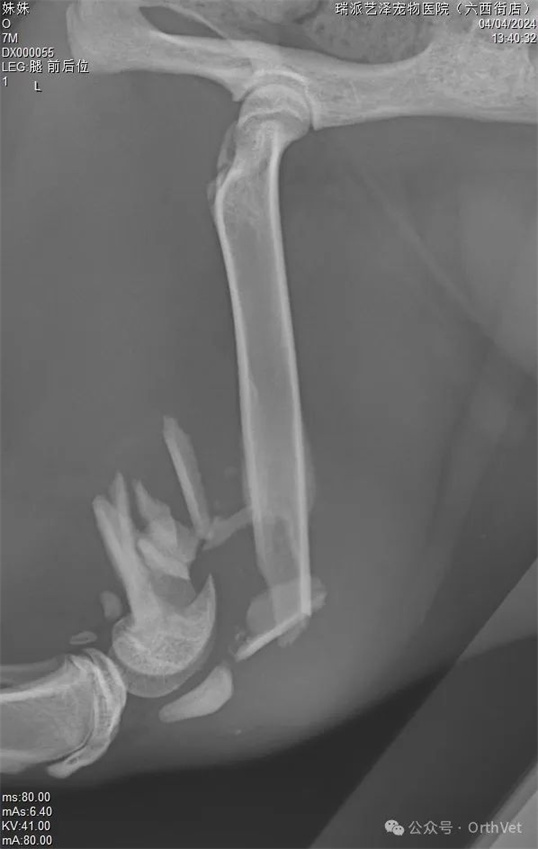

意外事故時有發生,導致各種災難性的後果。有時我們可以救治,但很多時候我們卻無能為力。這隻貓從高處跳下,遭受了嚴重的粉碎性骨折。手術的困難在於:幼貓需要考慮股骨的生長問題。幸運的是,6個月以上年齡的貓,股骨遠端生長板已經沒有太多剩餘的生長空間。其次,也要考慮動物術後無法有效限制運動,這涉及到股骨遠端髕股滑車和膝關節的活動。所採用的固定結構要考慮生長、機械穩定性和骨癒合等因素。基於上述考慮,股骨遠端採用內外雙板固定,既穩定又能中和骨骼的軸向壓縮力。 PRCL-6.5+5mm 骨板 內外固定採用股骨乾螺絲固定。採用膝關節外側入路,延伸至股骨中部。先行股骨內側固定,內側骨板不需過多塑形,再進行外側固定。在結構和力學穩定的情況下,盡量少用螺絲,盡量採用鎖定螺絲固定。術後需加強活動,避免肌肉沾黏及股四頭肌收縮。術後可使用預防性90-90繃帶固定3-5天。

以上是術前X光片